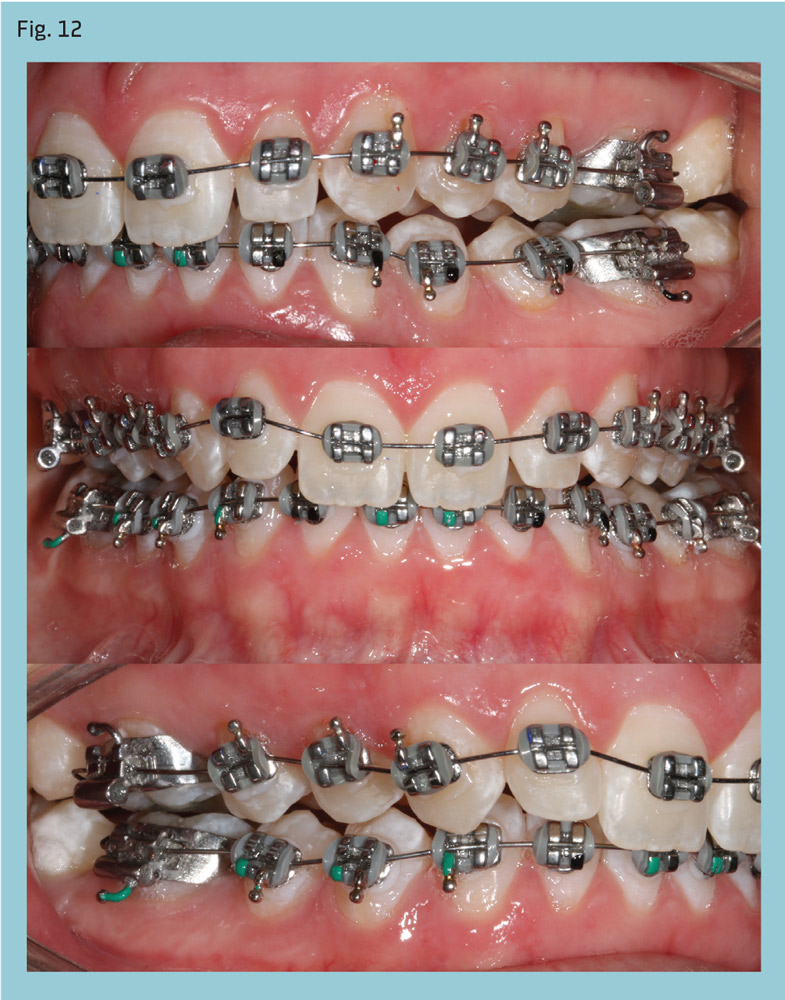

A 20-year-old woman presented with a Class II, Division 2, subdivision malocclusion with mild maxillary crowding (Fig. 11). Her overbite was almost 100 percent and lower midline was deviated to the left. Her condition was compounded by a left posterior crossbite. Cephalometric analysis revealed a dolichofacial pattern and mandibular retrognathia.

After four months of leveling and alignment, PowerScope was placed (Figs. 12-13). The Class II was corrected in three months (Fig. 14) and PowerScope removed. After another three months for coordinating the arches and detailing the occlusion, fixed appliances were debonded, completing 10 months of active treatment (Fig. 15).